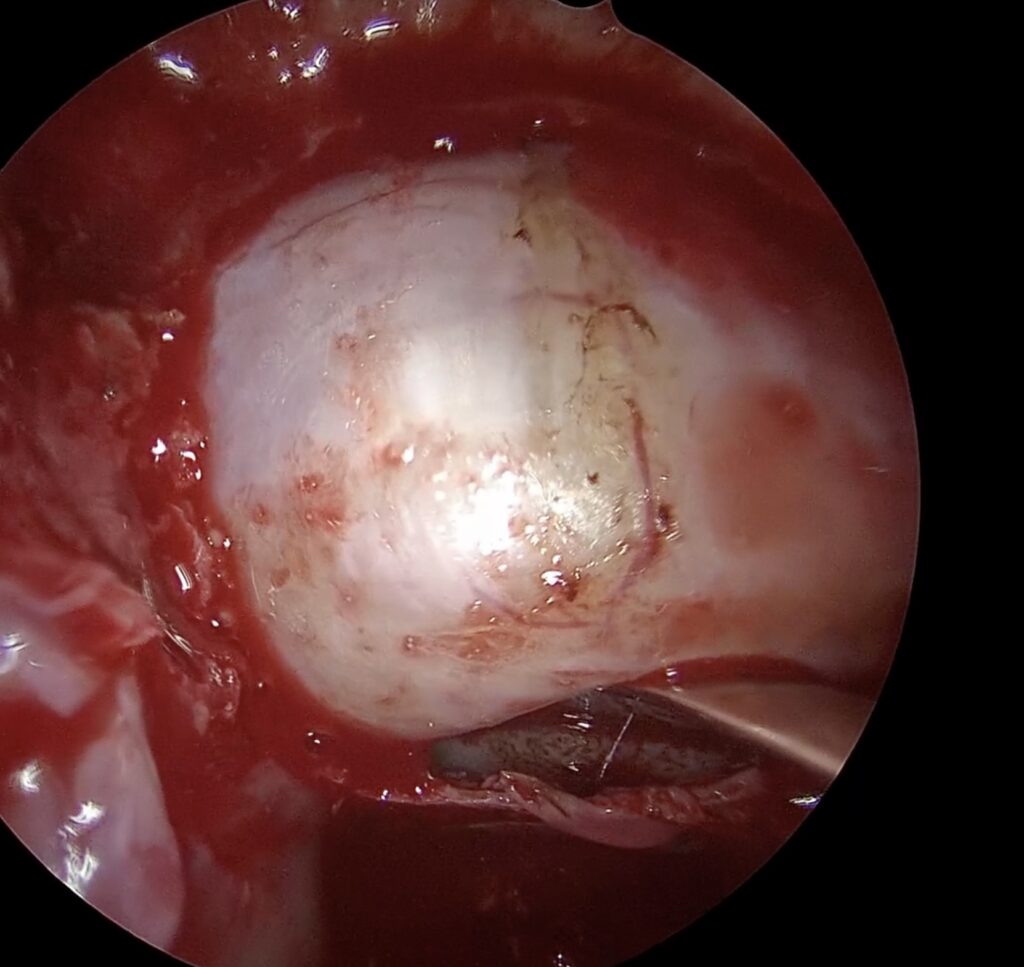

37歳女性 下垂体線腫を内視鏡手術しました。両耳側の視野欠損が回復しました。

若いですが、視野狭窄で発見された下垂体線腫を内視鏡で摘出しました。トルコ鞍前壁を十分に削除することで、上方の腫瘍残存をなくし、術後出血を防止できました。一過性に尿崩症が出現しましたが、コントロールされ退院されました。